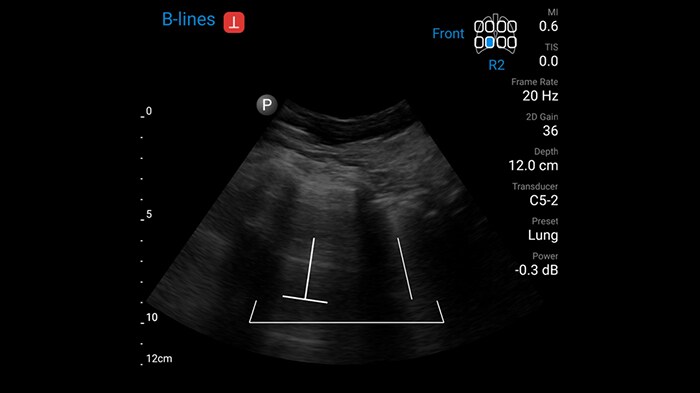

Now with AI-powered Auto B-line Quantification[1]

Auto B-line Quantification – unique to Lumify in handheld ultrasound – quickly delivers reproducible, reliable information that can enhance your confidence when making clinical decisions in critically ill patients with lung conditions.